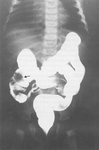

Upper GI contrast study demonstrating malrotation with volvulus. The duodenum fails to develop the normal anatomical C-loop. There is failure of contrast to pass, resulting in a characteristic bird beak consistent with acute mid-gut volvulus

From the collection of Dr KuoJen Tsao; used with permission